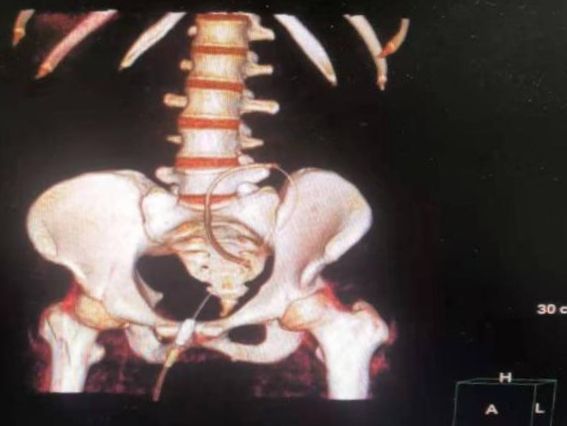

手术在门诊手术室进行,在上级医院专家指导下,东院肾脏内科孙芳副主任医师及贺海燕主治医师在超声引导下采用Seldinger法分别为两位患者成功实施了手术。患者术后恢复良好,腹膜透析治疗顺利。

术后CT三维重建观察导管位置